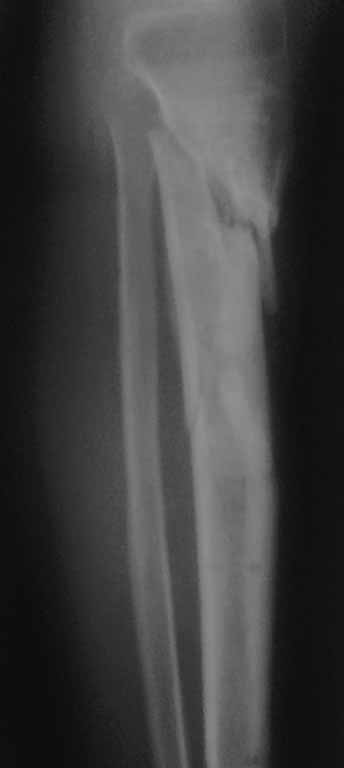

Жаль, что нет фасной проекции. Перелом на 2 уровнях, есть искривление костно-мозгового канала. Проксимальный отломок короткий. Вывод: лучше не штифтовать.

Спасибо за обсуждение.Отправил остальные R, изиняюсь за качество.

3.Перелом на 2 уровнях, есть искривление костно-мозгового канала. Проксимальный отломок короткий.

Ни одного снимка, где было бы видно коленный сустав.. Не совсем понимаю столь яростное отрицание стержня, проксимальный отломок не так уж и короток, 3 разнонаправленных винта войти смогут. Учитывая продление на диафиз, если выбирать между здоровенной пластиной и стержнем, ИМХО целесообразнее стержень.